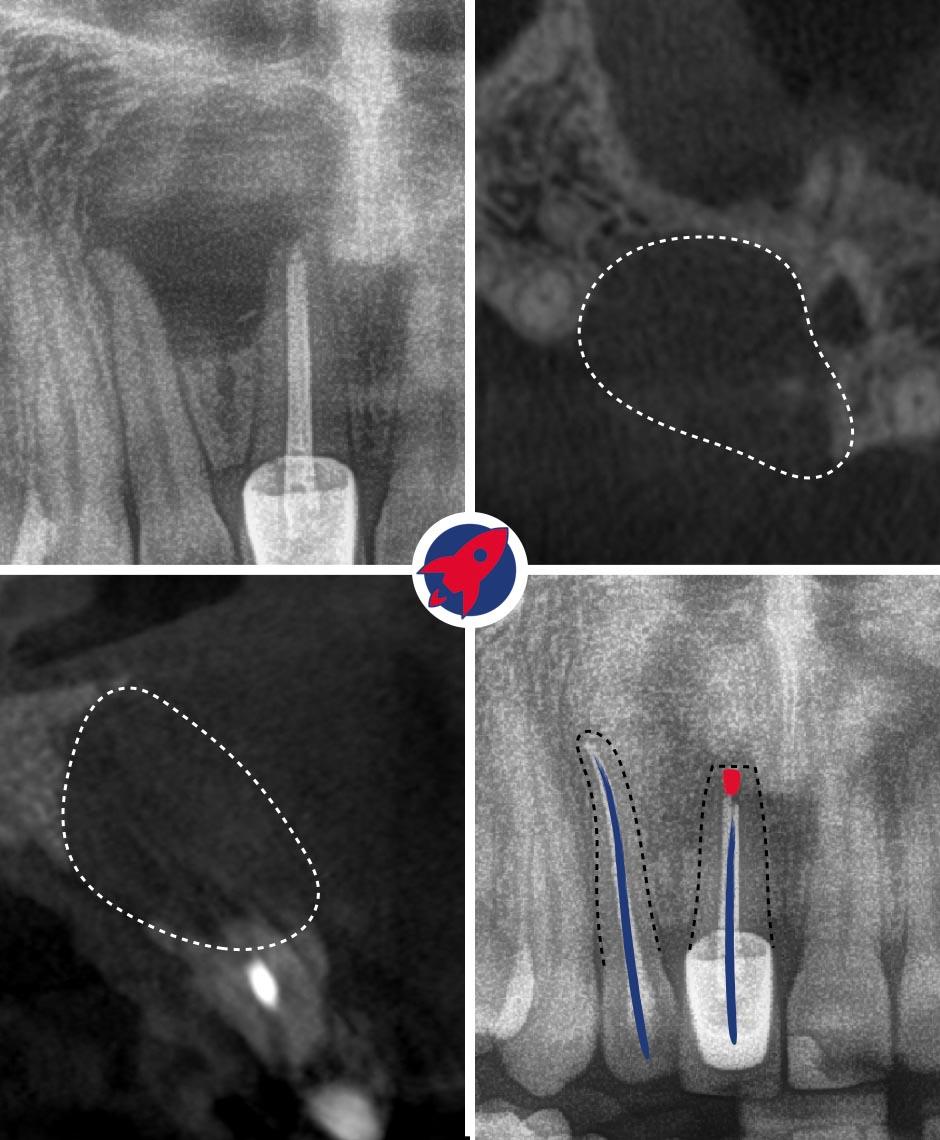

Vorgeschichte: Seit meiner Teenagerzeit kämpfte ich mit einem problematischen Backenzahn und war im Laufe der Jahre bei mehreren Zahnärzten. Ich habe diesen Zahn in meinem Heimatland entfernen und ein Implantat einsetzen lassen. Corona kam und aufgrund von Reisebeschränkungen verzögerte sich die Behandlung, was zur Folge hatte, dass das Implantat in der falschen Position einheilte und der dahinter liegende Zahn einbrach, was es unmöglich machte, eine Krone darauf zu befestigen.

Die Lösung: Dr. Horvath war in der Lage, einen langfristigen Plan zu entwickeln, um das Problem ein für alle Mal zu lösen, und mit der Hilfe seiner reizenden Frau konnten wir den notwendigen Platz für eine Krone schaffen, das Implantat entfernen und eine brandneue, maßgefertigte Brücke einsetzen, die buchstäblich in drei Stunden in 3D gedruckt wurde. Ein Teil davon, während ich schwanger war.